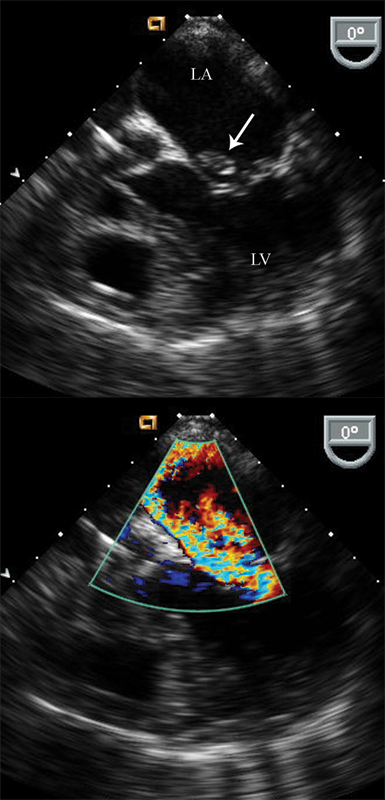

فحوصات تشخيصية لبعض امراض القلب والشرايين التاجية